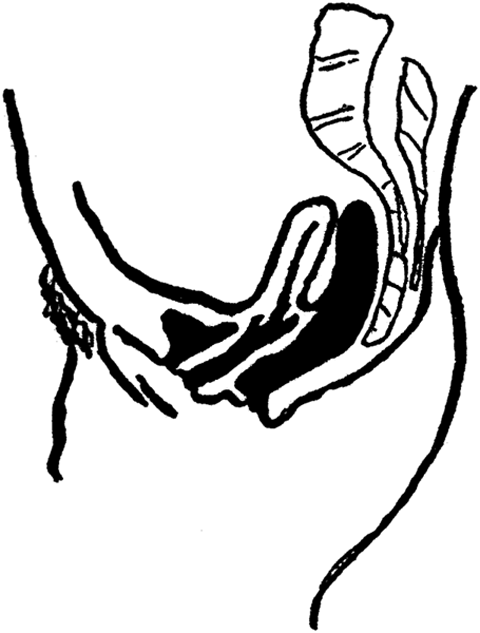

The Ovaries. The ovaries are the essential organs of reproduction. For it is they that generate the eggs, or ova, or ovules, which, after becoming fertilized or fecundated by the spermatozoa of the male, develop into children. Without the ovaries of the female, the same as without the testicles of the male (to which they correspond), no children could be begotten, and the entire human race would quickly disappear from our planet. The ovaries are two in number; they are embedded in the broad ligaments [35]which support the womb in the pelvis, one on each side of the womb. They are of a grayish or whitish pink color, and are about an inch and a half long, three-quarters of an inch wide, and one-third of an inch thick. They weigh from one-eighth to one-quarter of an ounce. Their surface is either smooth or rough and puckered. Think of a large blanched almond and you will have a pretty fair idea of the size and shape of an ovary.

Ovary.